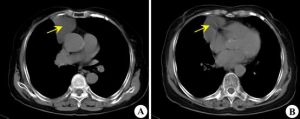

2.CT表現:

①2/3心包囊腫位於右心隔角區余見於左心膈角心後等處。

②病變通常與心包相連但少數帶蒂而與心包無明顯連線。

心包囊腫④增強檢查病變無強化。